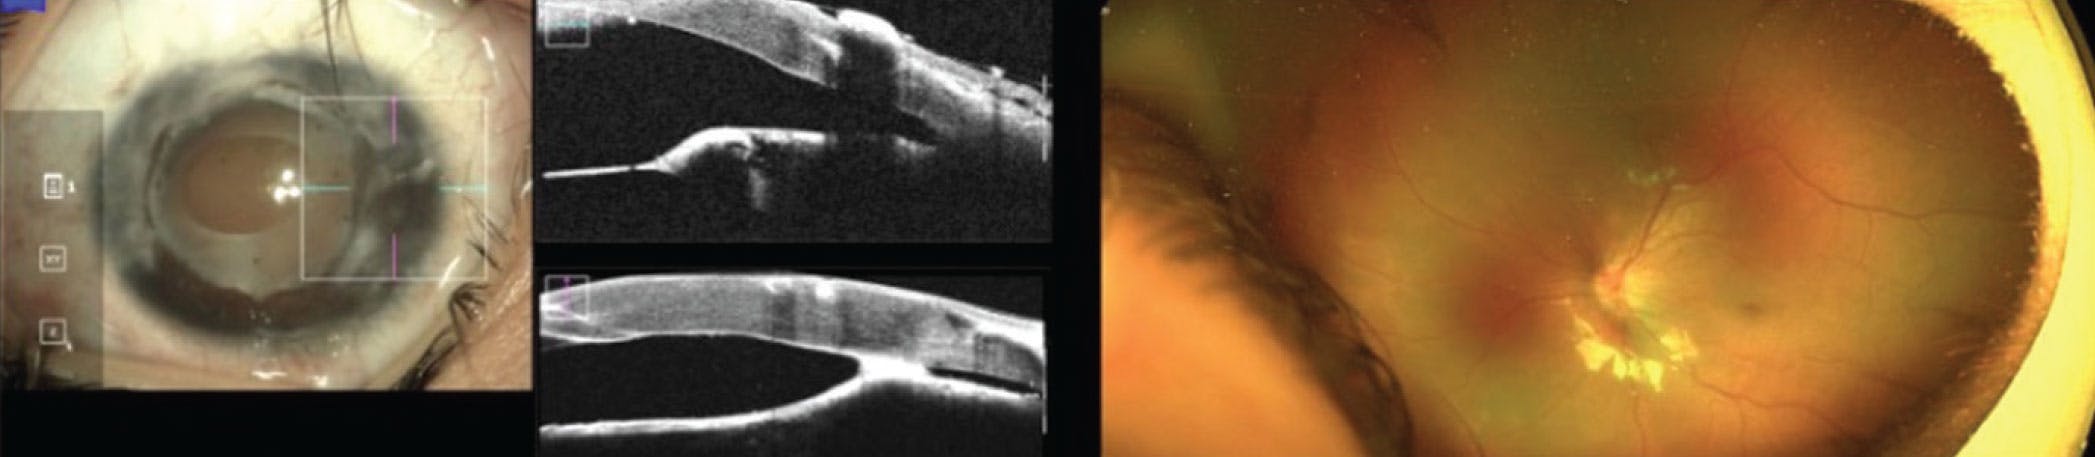

Postoperatively, the retina started to flatten and unfold, and the disc and macula could be seen in all four eyes after 3 and 2 months, respectively. Both patients could follow and fixate on objects several months later (Figures 3 and 4).

<p>Figure 3. The right (A) and left (B) eye of the patient in case 1 at baseline versus 1 month post-intravitreal injection and 3 months after LS-PPV.</p>

Figure 3. The right (A) and left (B) eye of the patient in case 1 at baseline versus 1 month post-intravitreal injection and 3 months after LS-PPV.

<p>Figure 4. The right (A) and left (B) eye of the patient in case 2 preoperatively (insets) versus 2 months after LS-PPV.</p>

Figure 4. The right (A) and left (B) eye of the patient in case 2 preoperatively (insets) versus 2 months after LS-PPV.